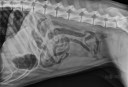

Archives de catégorie – Ils ont mangé quoi ?

• Ils ont mangé quoi ? (18)